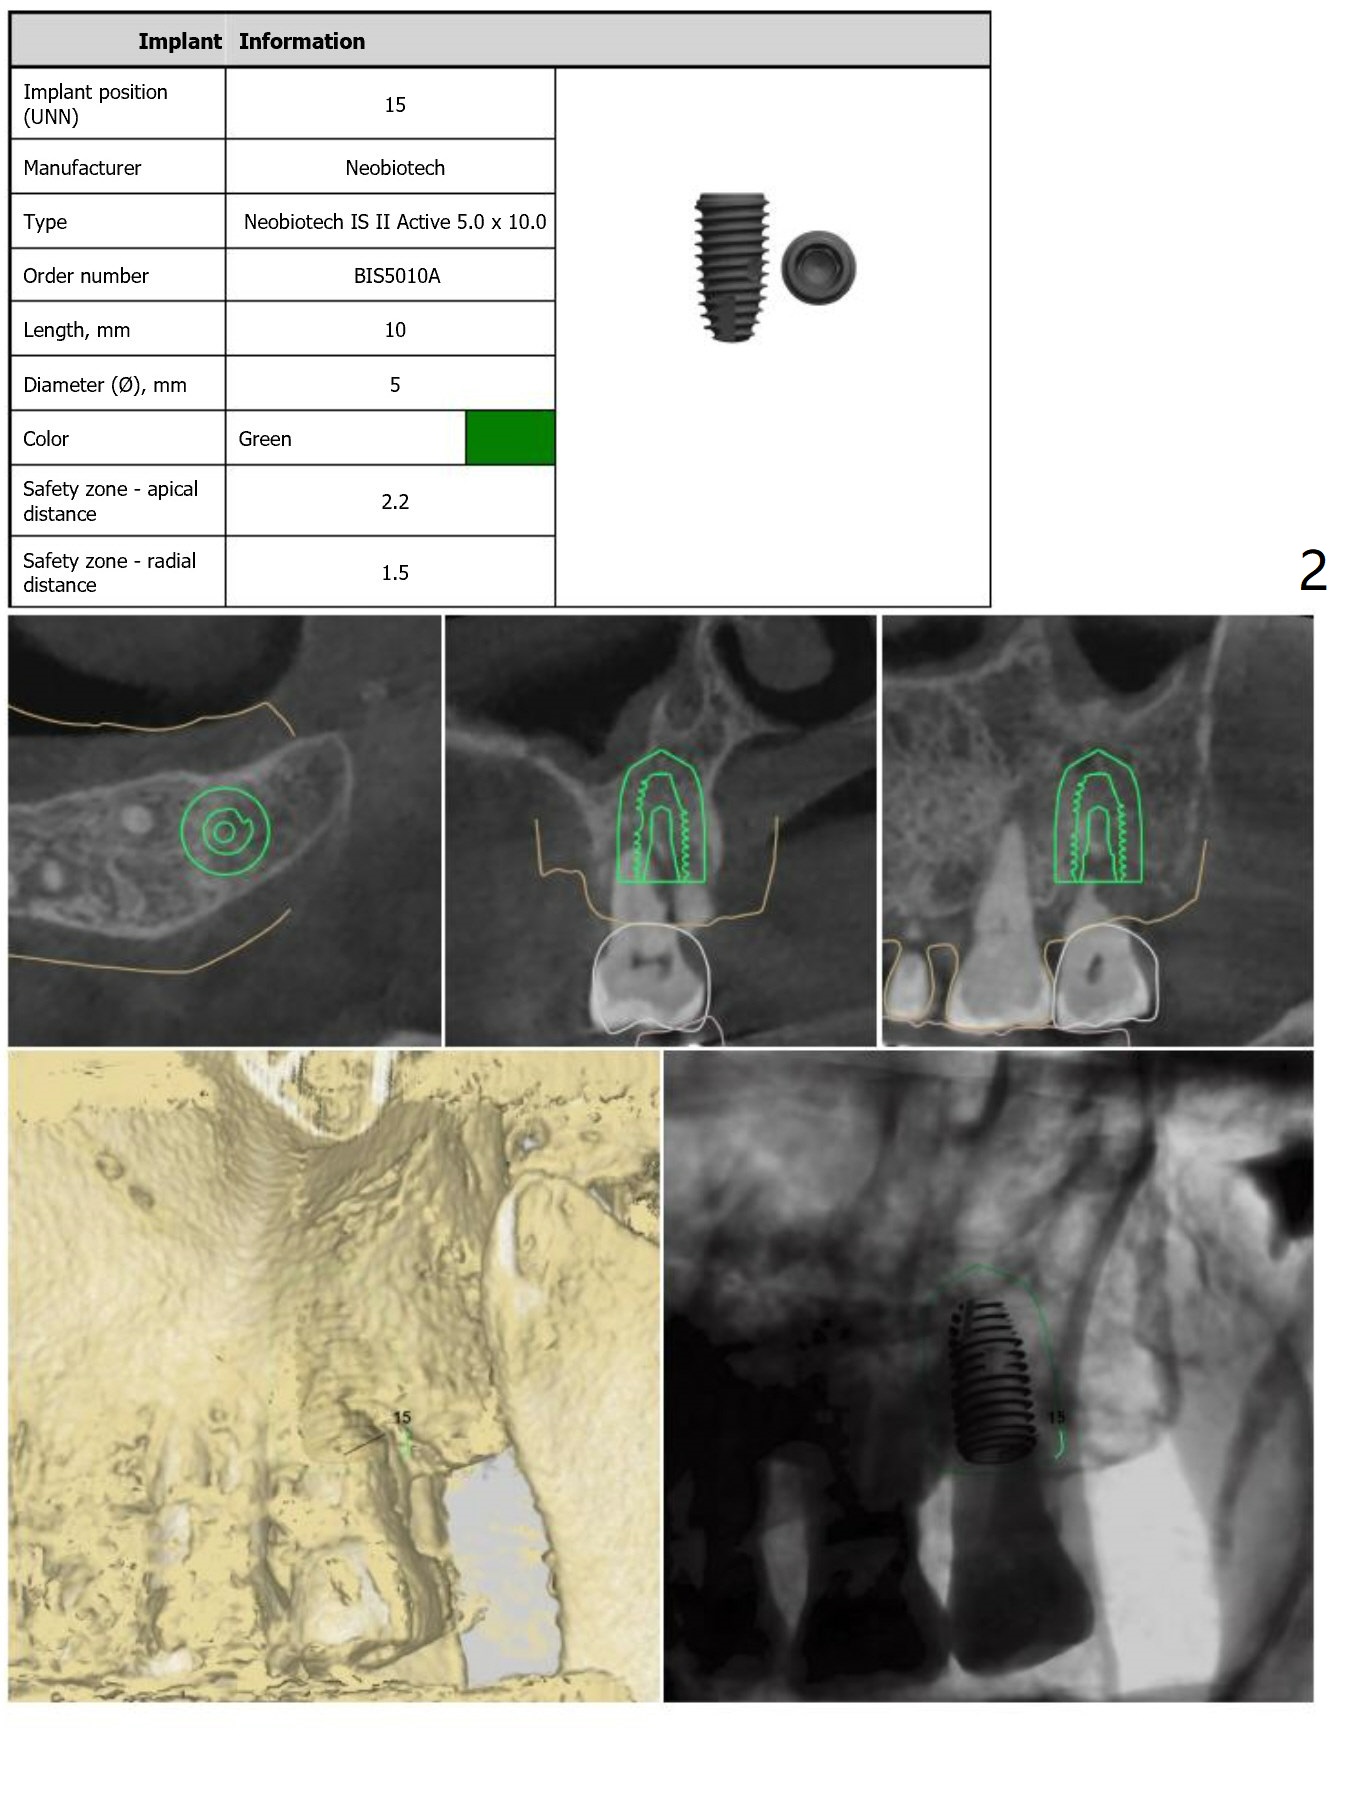

Return to Upper Molar Immediate Implant, Trajectory II

Xin Wei, DDS, PhD, MS 1st edition 01/31/2019, last revision 09/03/2019